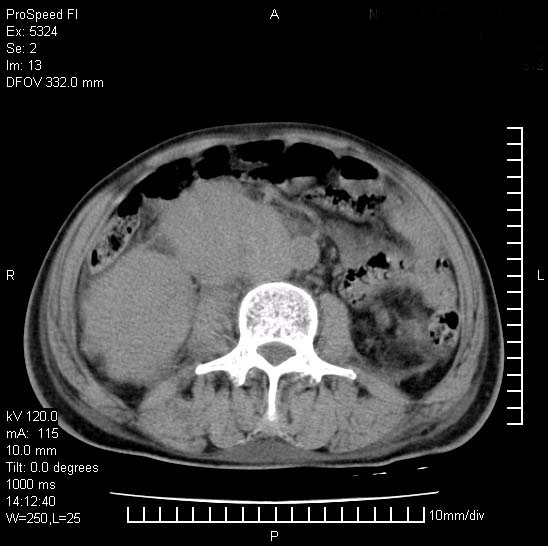

患者阴囊肿大14月,腰痛2个月,咳嗽,咳痰1周,患者现在肾功异常,做增强有些担心,我们用的是欧乃派克.

右侧肾癌伴腹膜后淋巴结转移!

右侧肾癌后腹膜转移,腹腔少量积液

腹膜后淋巴结肿大包饶腔静脉,双肾病变,建议增强

双肾均有软组织密度舯物,腹膜后淋巴结肿大包饶腔静脉------考虑为恶性占位病变,转移瘤可能。

支持:双肾均见软组织密度肿块影,腹膜后淋巴结肿大包绕腔静脉------考虑为恶性占位病变,转移瘤可能。

1)考虑双肾恶性肿瘤(肾癌?)。2)腹膜后淋巴结肿大,多为肿瘤转移所致。

腹腔积液,双肾均有稍高密度肿块,主动脉旁广泛淋巴结肿大,融合,无显著肿块坏死征像,多考虑淋巴瘤累及双肾,不排除肾癌伴转移(肾癌这么大应该较多坏死了),另阴囊肿大,不知是实质肿大还是阴囊积液,如是是积液,多为腹腔肿块压近睾丸静脉所致,如是是实性的,多为淋巴瘤

1、淋巴瘤,双肾转移瘤;2、双侧肾癌,伴有腹膜后淋巴结转移。